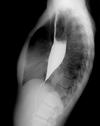

Grey Turner’s sign

Flank ecchymosis

Acute pancreatitis